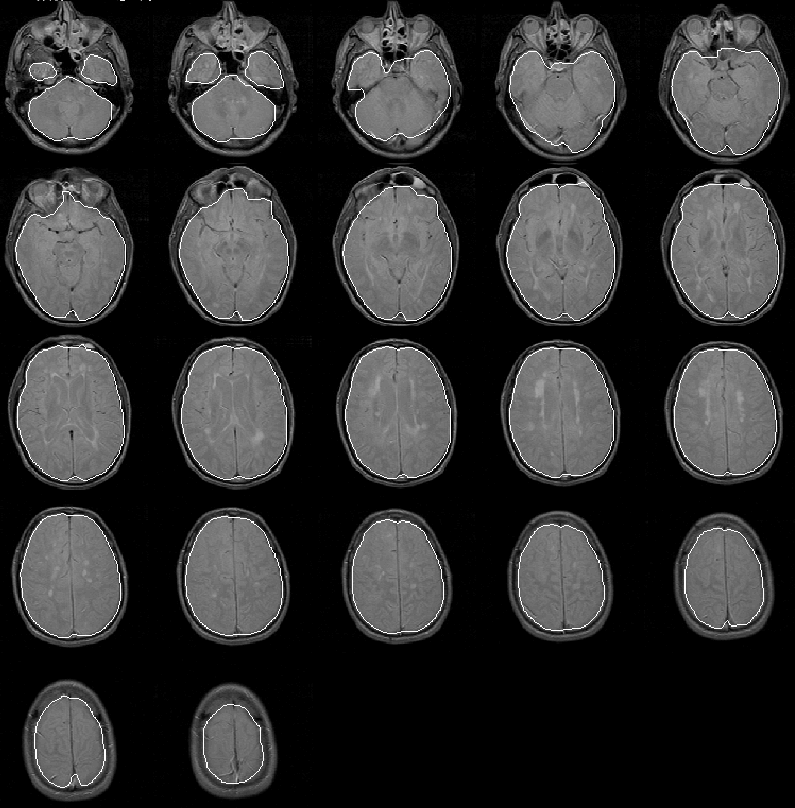

Figure 8.21 shows the final brain mask for Data Set 2 overlaid on the PD-weighted MR scan. Again the intracranial boundary is detected exceptionally well in all slices. The final brain mask contains no remarkable errors.

Figure 8.21: The final brain mask for MRI Data Set 2 overlaid on the PD-weighted scan.

Figure 8.22 shows the regions in slice 11 that a radiologist identified as brain tissue. At least for slice 11, the automatically detected intracranial boundary appears to outline the brain accurately.

Figure 8.22: (a) Brain tissues in slice 11 of MRI Data Set 2 identified by a radiologist. (b) The automatically detected intracranial boundary.

A quantitative analysis of the intracranial contour for just this slice would be statistically insignificant in terms of the whole MR volume. Expert validation of the contours produced for the entire volume is necessarily delayed for future work.